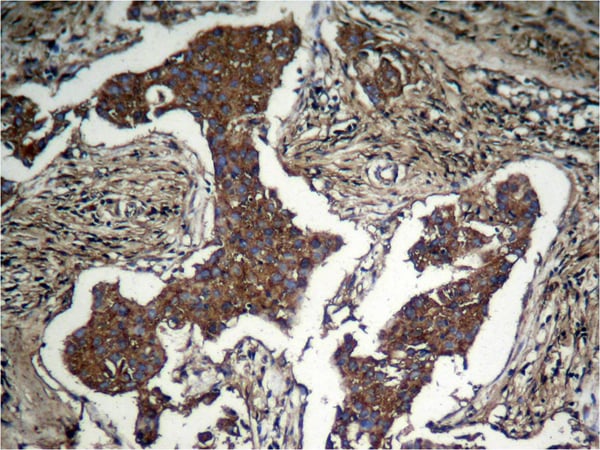

IHC (Immunohistochemistry)

(Immunohistochemical analysis of paraffinembeddedhuman Lung carcinoma tissue usingAkt (Phospho-Ser473) Antibody.)